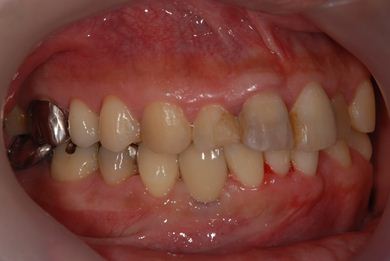

| 性別/年齢 | 男性 / 37歳 | ||||||||||||||||||||||||||||||||

| 主訴 | 数年前に神経を抜く治療をした下顎の歯が、1年ほど前にうずきを感じて治療をした際に、完全に治療するのは難しいと言われた。その歯がぐらつくように感じ始めたので、相談のために来院。 | ||||||||||||||||||||||||||||||||

| 治療内容 | インプラント1本(GBR)、メタルボンドセラミック1本 | ||||||||||||||||||||||||||||||||